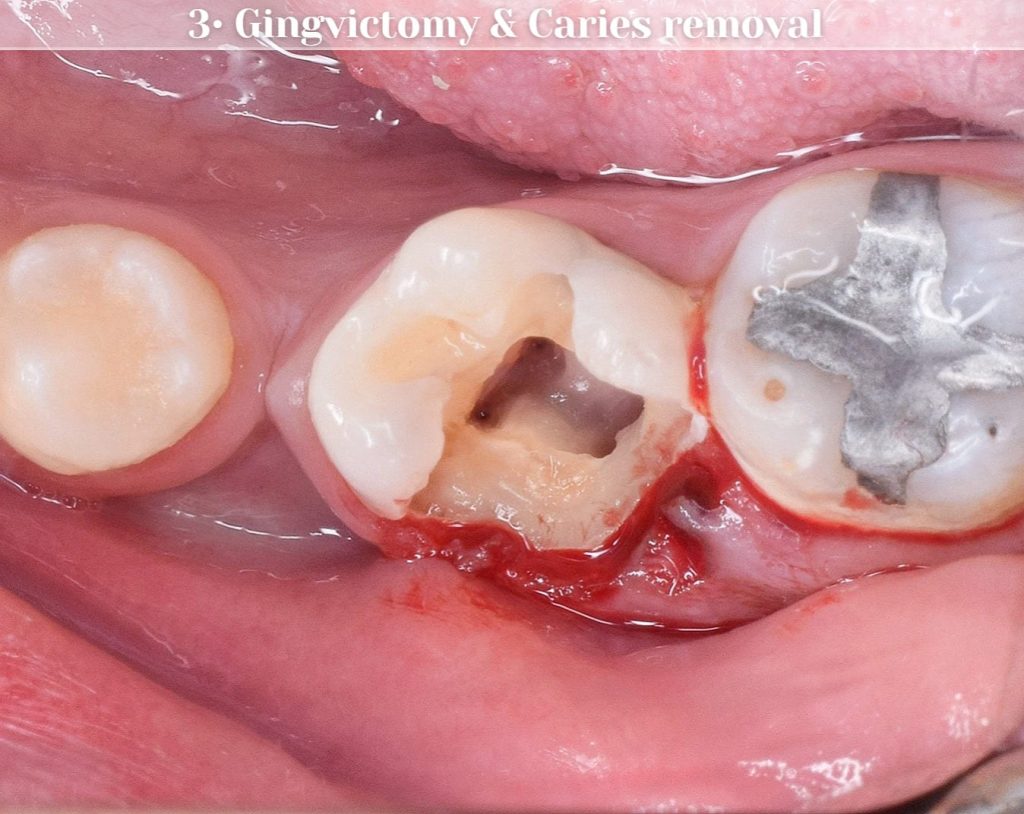

Gingivectomy - Gingival polyp removal

Gingivectomy, removing gingival polyp for helping us to isolate the tooth and make a good isolation before Rct, I make pre endo build up, then RCT done, Then i did a direct composite filling “OVERLAY”.